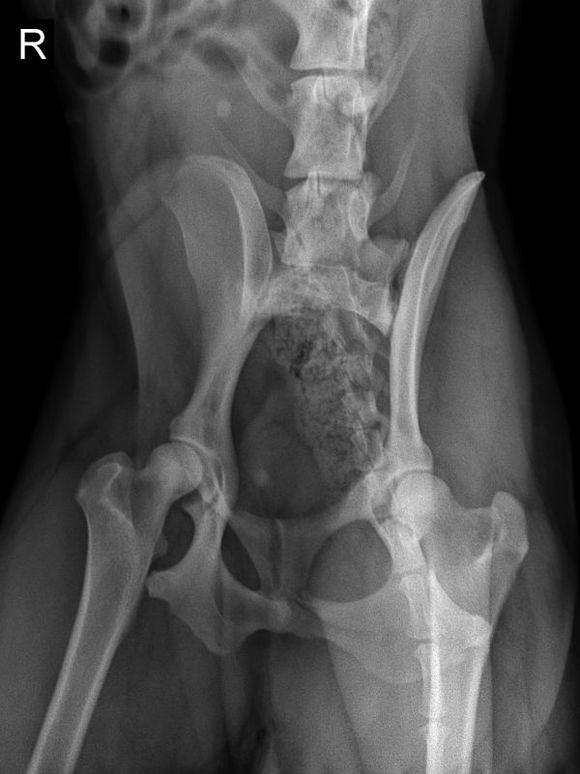

可是这一检查就了不得了,这查出来居然说是狗狗太胖了,挤压到了背部脊椎神经,所以才感到痛苦,需要开始给狗狗节食减肥了!